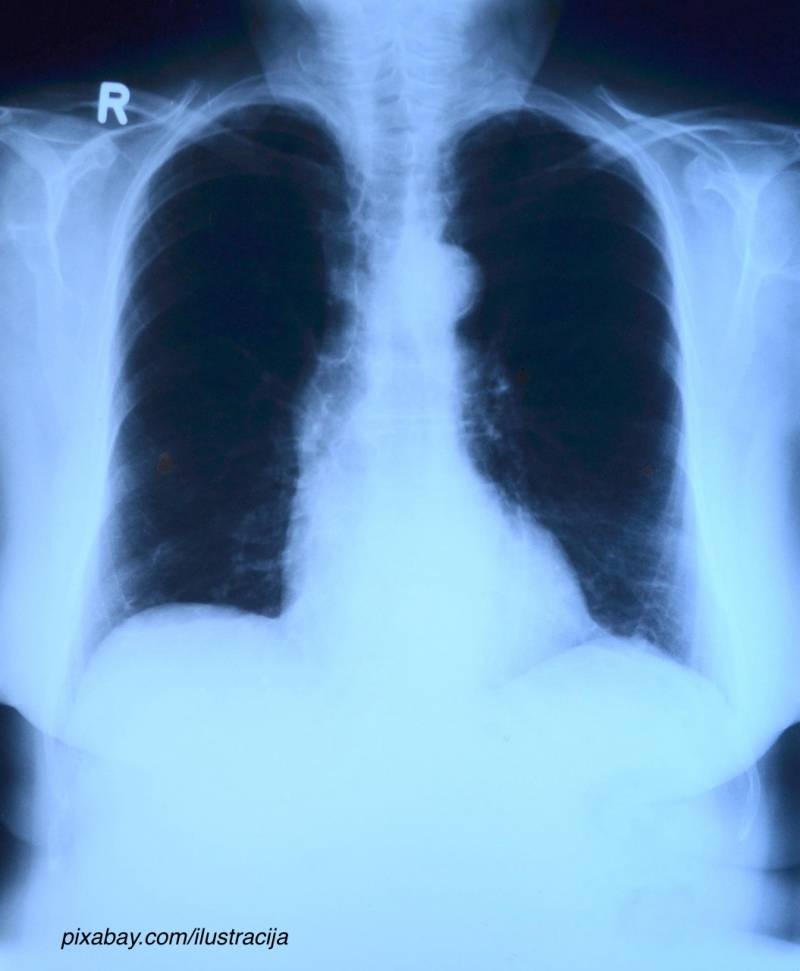

Karcinom pluća je bolest koja nastaje kada se ćelije u plućima nenormalno množe. Postoje dva glavna tipa: mali ćelijski karcinom i veliki ćelijski karcinom. Glavni uzrok ove bolesti je pušenje, ali se može javiti i kod nepušača.

Karcinom pluća se kod čak 60% pacijenata otkriva tek kada je bolest već uznapredovala, što otežava lečenje. Prvi simptomi, kao što su kašalj, umor ili otežano disanje, često su nespecifični i mogu se lako pripisati manjim problemima, posebno kod pušača koji su navikli na te tegobe.

Lekari ističu da organizovani skrining za rak pluća može značajno poboljšati pravovremenu dijagnostiku i povećati stopu preživljavanja.

✅ Važno je redovno odlaziti na lekarske preglede i raditi snimanja pluća, posebno ako imate faktore rizika. Preporučujemo prestanak pušenja i zdrav način života kao najbolju prevenciju. Ako primetite simptome, obavezno se obratite lekaru, jer je vaše zdravlje najvažnije.